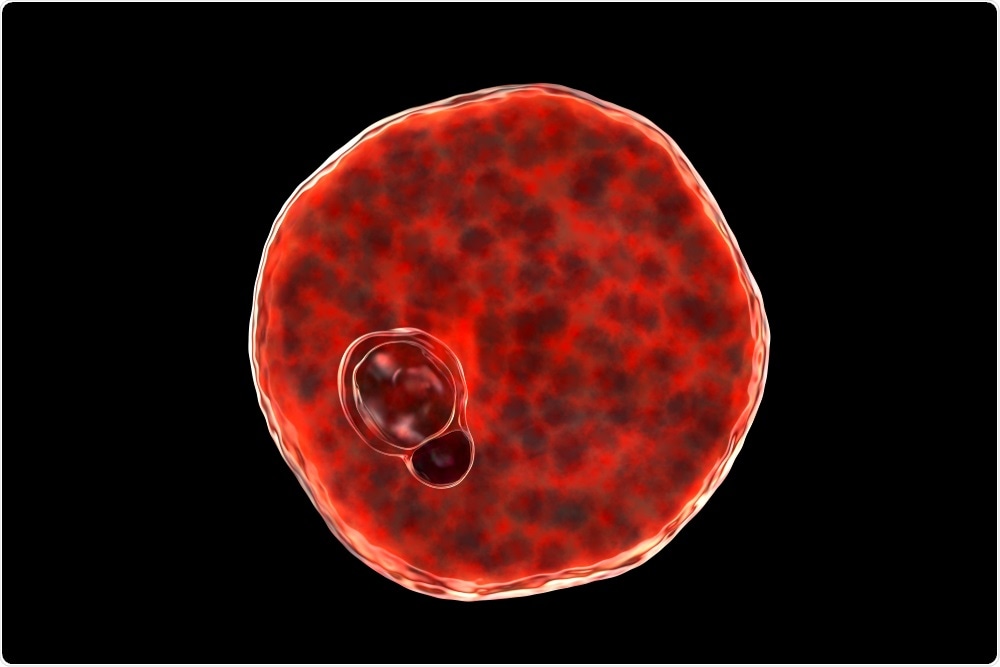

Plasmodium vivax inside red blood cell. Image Credit: Kateryna Kon/Shutterstock.com

Once in the liver, the Plasmodium sporozoites undergo intrahepatic development to become mature merozoites. These mature merozoites enter a cyclic blood stage where they continuously infect RBCs, thus leading to the various signs and symptoms associated with this infection.

By maintaining much of their existence within the enclosed environment of the RBCs, the parasite is protected against any host immune response that would otherwise lead to their demise. It is only when the parasite is present outside of the RBC, which can occur during traversal or immediately prior to host cell invasion, that it is vulnerable to attack by the host’s immune system.